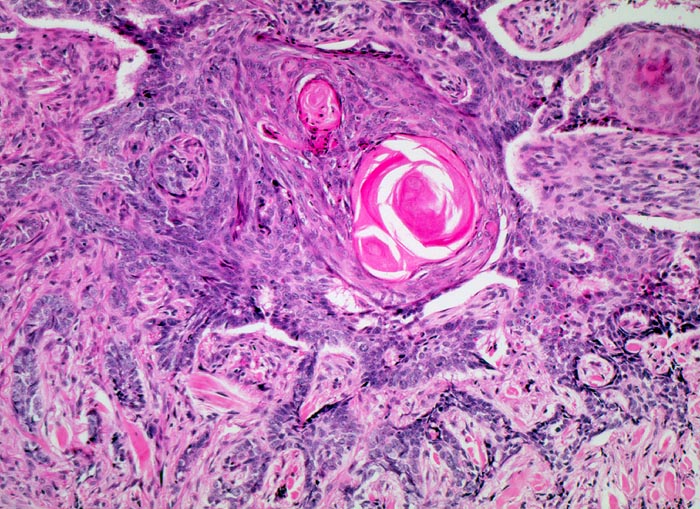

solides Basalzellkarzinom mit Verhornung

Zackig begrenzte Epithelverbände aus basaloiden Zellen mit randständiger Palisadierung. Hornperlen im Zentrum der grössten Epithelverbände.

Stark ulzerierender Wangentumor links

Histologie

100